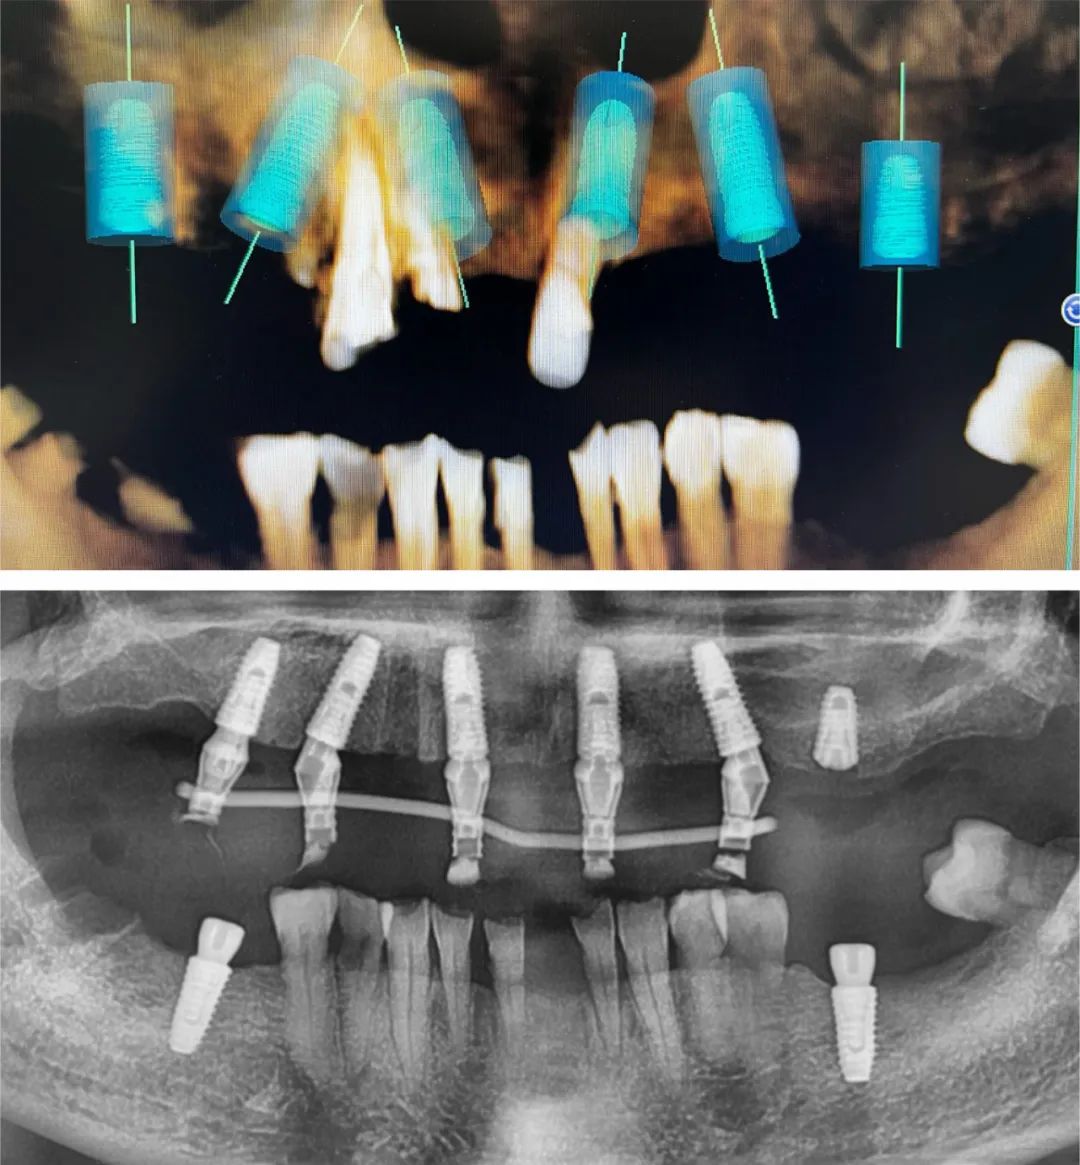

2017年,張嘉宇開始嘗試數字化種植。彼時,口腔種植技術已在國內逐步普及,但數字化對于大多數種植醫生來說還是一個陌生的領域。

“數字化種植包括數字化口腔掃描、數字化種植方案設計和數字化導板導航手術等幾個環節,它比傳統的人工取模更精準、更舒適,手術不需要翻瓣,創傷小,是對現有種植技術的一個有益的補充。”

“單顆或幾顆牙齒缺失時,口腔里還有足夠多的牙來固定導板,采用數字化導板導航進行種植還是比較精準的,但如果缺的牙比較多,導板的固定只能采用牙和口腔黏膜的混合支持式,因為牙和黏膜的強度、彈性是不一樣的,可能會影響到導板的穩定性,從而影響種植的精準度。另外,導板的硬度也會影響到種植效果。”

張嘉宇認為,復雜的種植病例和需要種植位置極度精確的,差誤不能超過0.5毫米的病例,數字化導板導航種植是一個不錯的選擇。

“我每一臺手術之前都要分析到位,不打無準備之仗。因為之前機構的手術室沒有顯示屏,手術時看不到患者的CBCT,只能憑著記憶和肉眼觀察去做,對于難度較大的案例,我都會在術前把模擬植入的位置擺好,存在手機里反復熟悉,做到心中有數。”